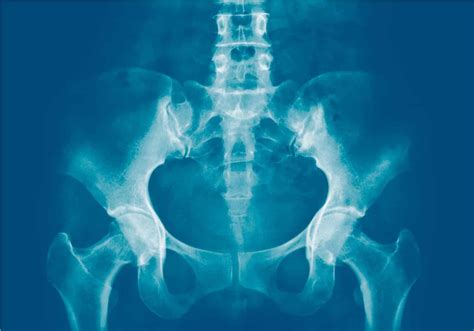

• Imaging studies, such as X-rays, MRI, or CT scans, to visualize the joint and surrounding structures

In some cases, an Xray Si Joint may be recommended to confirm the diagnosis and rule out other potential causes of pain. This imaging technique provides detailed images of the joint and can help identify any abnormalities or degenerative changes.